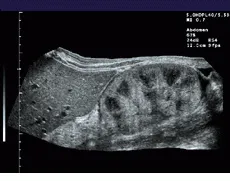

To increase the FOV in its Elegra system, Siemens combines the real-time imaging capability of modern ultrasound transducers with the ability to generate images over large fields of view. To do so, the system registers sequentially acquired image frames, estimates transducer motion, and constructs a panoramic view of the extended FOV in real time (see Fig. 1).

FIGURE 1. To extend the field of view (FOV) of ultrasound, the system registers sequentially acquired image frames and constructs a panoramic view of the extended FOV in real time. A comparision between a standard linear field of view of a renal transplant (bottom) and a wider, panoramic field of view (top) illustrates the effects of the process.